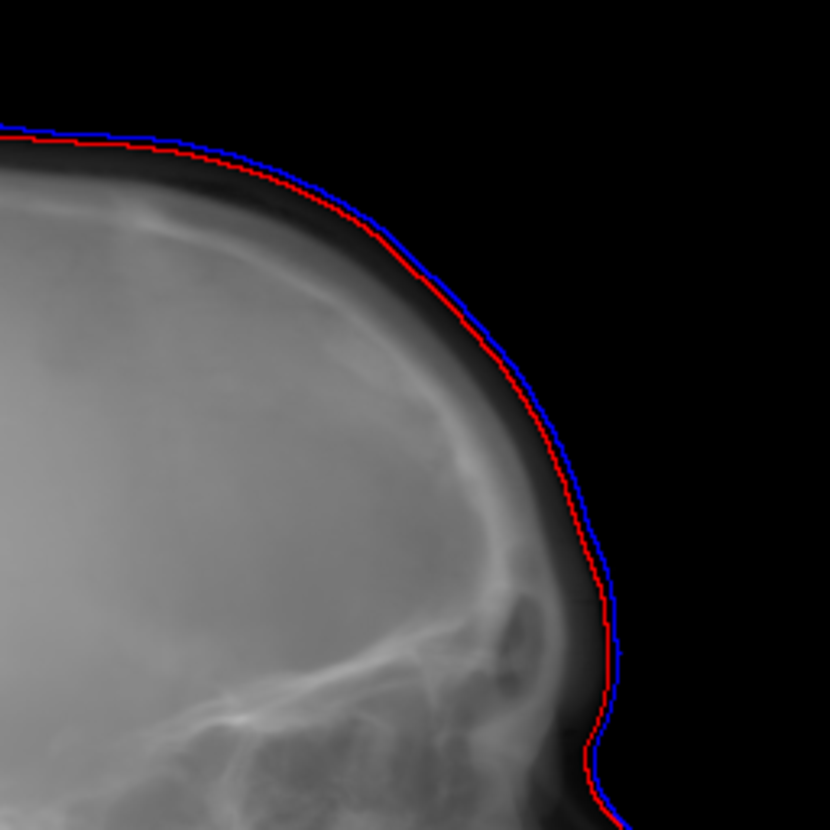

To combine such dual projection information, we convert the patches from 0superscript00^{\circ} and 180superscript180180^{\circ} cone-beam projections to 3-channel patches forming RGB color patches. The 0superscript00^{\circ} patch is used for the red and blue channels, while the 180superscript180180^{\circ} patch is used for the green channel. The 0superscript00^{\circ} patch instead of the 180superscript180180^{\circ} patch takes two channels, since the target cephalograms are also acquired in the 0superscript00^{\circ} view in our setting. In the RGB patch, the intensity difference between the 0superscript00^{\circ} patch and the 180superscript180180^{\circ} patch is revealed by the color: grey areas have the same values for the three channels, indicating that the intensity values from the 0superscript00^{\circ} and 180superscript180180^{\circ} patches respectively are close to each other, while green areas indicate that the 180superscript180180^{\circ} patch has larger values and magenta areas indicate that the 0superscript00^{\circ} patch has larger values. An example is displayed in Fig. 5, where Figs. 5(a) and (b) are the 0superscript00^{\circ} and 180superscript180180^{\circ} patches respectively, Fig. 5(c) is the RGB patch as the input of the neural network, and Fig. 5(d) is the corresponding target output of the neural network.

Fig. 5: One patch example for dual projections to one cephalogram synthesis: (a) the first quadrant patch from the 0superscript00^{\circ} rebinned cone-beam projection; (b) the first quadrant patch (horizontally flipped) from the 180superscript180180^{\circ} rebinned cone-beam projection; (c) the RGB patch using (a) for the red and blue channels and (b) for the green channel, where the colourful areas highlight the difference between (a) and (b); (d) the target patch synthesized by our proposed volume-to-cephalogram method.